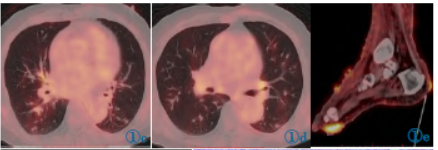

18F-FDG剂量为6.73mCi,注射后1h检查。PET/CT图像采集包括CT平扫和PET扫描。CT扫描参数:电压120keV,电流自动毫安秒,螺距0.6,层厚5mm。PET扫描,2min/床位。扫描范围颅顶至足底。图像采用CT扫描数据衰减矫正,图像重建采用有序子集最大期望迭代法。18F-FDGPET/CT显像示双肺见多发不规则结节,沿肺纹理分布,最大约10mm×15mm,轻度代谢增高,SUVmax为1.9,气管血管旁间质增厚;双下肢皮肤多发不规则结节状增厚,双足多见,代谢异常增高,SUVmax为8.0,伴双下肢水肿(图1)。

图1 18F-FDGPET/CT显像图。图1a,1b为体部及下肢MIP图,下肢见多发异常高代谢结节;图1c,1d见双肺多发结节,大部分形态不规则,沿肺纹理分布,轻度代谢;图1e,1f见双足皮肤多发不规则、结节状增厚,代谢异常增高。